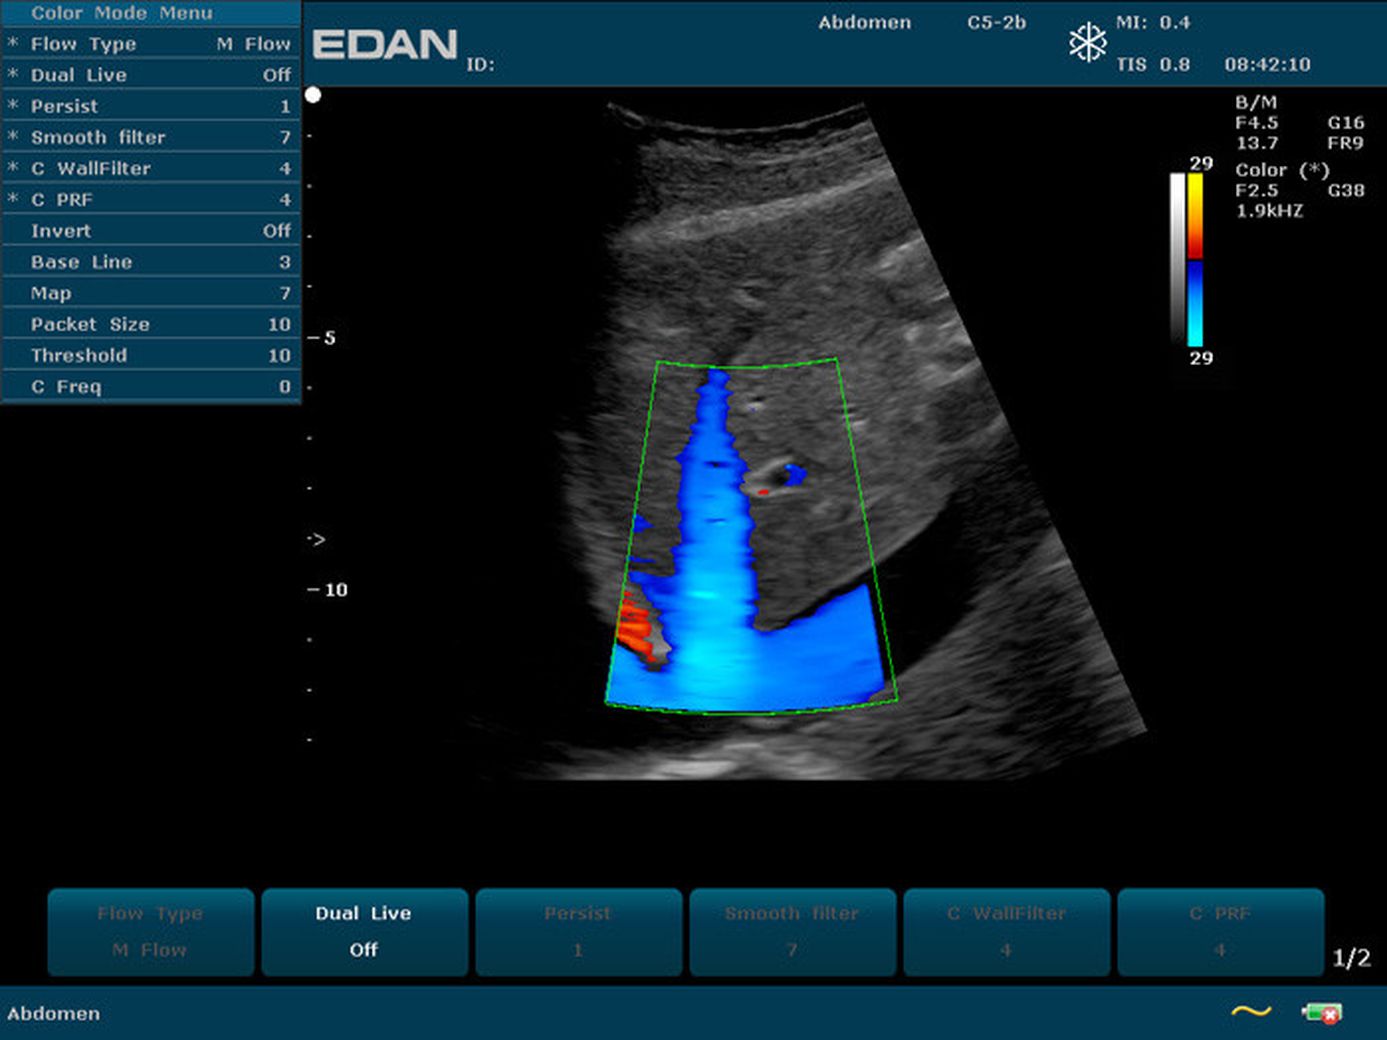

Прибор u2 143 фото